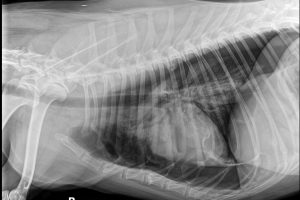

Presentation: Signalment: 4-year-old male neutered Corgi History: No prior medical conditions. 10-day history of paraplegia. Physical findings: No significant joint abnormalities. Mentally appropriate. Forelimbs normal. Non-ambulatory paraplegic, extensor rigid …